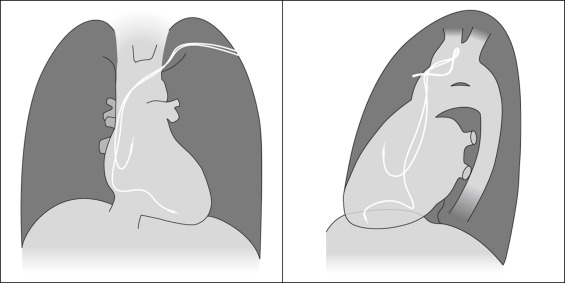

Endocardial Pacer Leads

The position and integrity of endocardial pacer leads should be verified, especially when pacemaker dysfunction is clinically suspected ( Graphics 23-1 to 23-4 ; Figs. 23-1 to 23-15 ).The most common cause of pacemaker dysfunction that is apparent on the chest radiography is distal lead displacement/misplacement.

With a right atrial lead , the tip should be in the right atrial appendage.

With a right ventricular lead , the tip should lie anteriorly at the apex of the heart.